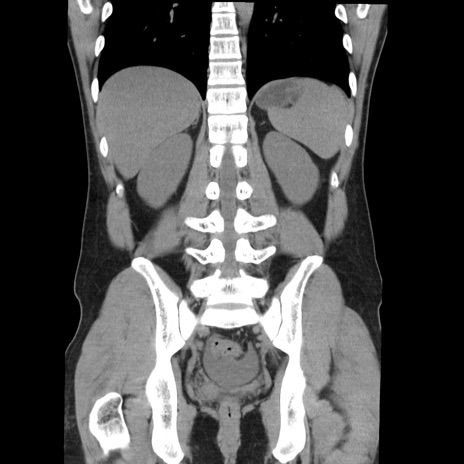

横断像

【症例】20歳代 男性

【主訴】心窩部痛

【現病歴】今朝より上腹部痛あり。一旦軽快していたが再度出現したため救急要請。昨日夕に白身の魚を含む刺身を食べた。

【身体所見】BP 136/89mmHg、HR 74/min、BT 37.0℃、腹部:膨満、軟、心窩部に圧痛あり。反跳痛なし、筋性防御なし、腸雑音やや亢進あり。

【データ】WBC 17700、CRP 0.48